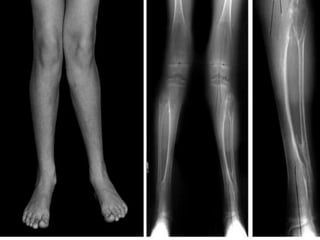

RODILLA VARA

Afección que se da en los

niños que nacen con las

piernas arqueadas hacia fuera

debido a su posición plegada

en el útero.

Es típica en niños por debajo

de los 2 años.

Pueden ser causadas por

manifestación de:

• Raquitismo, el cual es

ocasionado       por    una

deficiencia de vitamina D.

• Displasias Oseas

• Fracturas que no sanan

correctamente

Las rodillas no se tocan

cuando el individuo está de

pie con los pies juntos y son

simétricas

Evaluar al niño al menos cada 6 meses